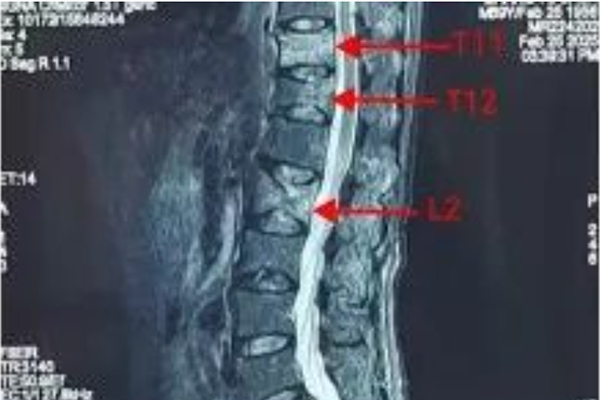

术前腰椎核磁检查

患者因持续腰痛两月辗转多家医疗机构保守治疗未果,经榆次区中医院骨伤科三维CT及MRI检查,确诊为三处新鲜椎体压缩性骨折。面对手术复杂性和风险,科室在凌云副院长指导下组织多学科会诊,制定个性化微创方案。手术由任大威、张瑾峰医疗团队主刀,在C型臂精准导航下,仅用90分钟完成三椎体骨水泥灌注,术中出血不足20ml,创口仅3个5毫米穿刺点,完美践行“以最小创伤解最大病痛”微创理念。